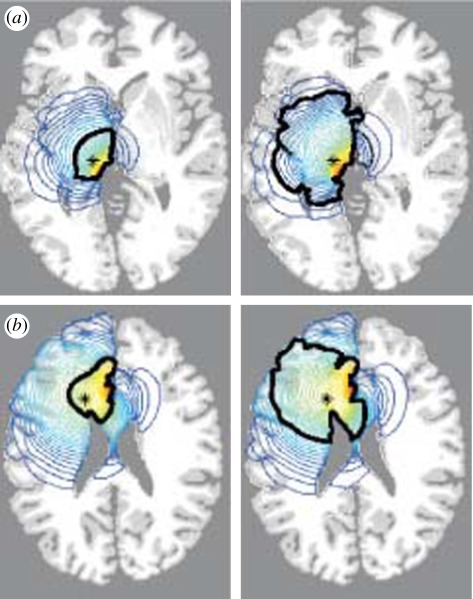

Using the model, two individual patient brain scans allow the key model parameters, namely the diffusion, D, and the cell growth, ρ, to be calculated [63,64]. With these parameter values we can predict the growth of such brain tumours and importantly estimate key aspects of the tumour's growth and response of individual patients to different treatment protocols prior to their use. Figure 4 is a computed solution of equation (5.2) in an anatomically correct brain: it shows the detectable tumour at death and the spread of the tumour cells beyond what can be detected by the most accurate current computed tomography (CT) or magnetic resonance imaging (MRI) techniques. Simulations of the model thus greatly enhance current imaging techniques to whatever level of cancer cell density is required. The model analysis shows how fast the tumour grows and, importantly, where in the brain [64,65].

Figure 4.

Computed solutions of equation (5.2) in a three-dimensional anatomically accurate brain. These show the horizontal section of the virtual human brain through the site of the original tumour (`plus’ in (a), `asterisk’ in (b)). The left image in each is the tumour at diagnosis while the right image is the same tumour at the time of death. The thick black contour defines the edge of the tumour that can be detected by enhanced CT. The blue contours outside this black line represent lines of constant cancer cell densities peripheral to the imaging limits. (a) Tumour in grey matter: the time from diagnosis to death is approximately 8 months. (b) Tumour in white matter: the time from diagnosis to death is approximately 5 months. (Figures adapted from [64].)